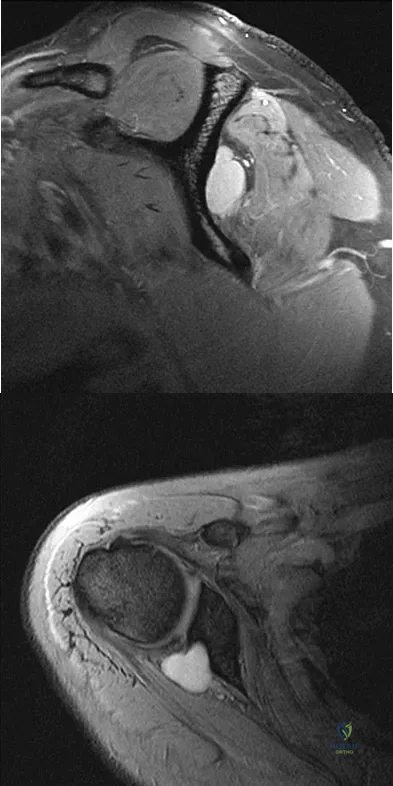

Question 18 High Yield

Figure 6 shows a sagittal oblique MRI scan. The arrow is pointing to what structure?

Detailed Explanation

A 47-year-old male tennis player has pain in his nondominant shoulder that has failed to respond to 4 months of nonsurgical management. Examination reveals acromial tenderness and pain at the supraspinatus tendon insertion. He has a positive impingement sign, pain on forward elevation, and minimal cuff weakness. The MRI scans are shown in Figures 30a and 30b. To completely resolve his symptoms, treatment should consist of

Explanation

Figure 14 shows an intra-articular gadolinium-enhanced MRI scan of a 52-year-old woman who has stopped playing tennis because of pain in her left shoulder while serving. What is the most likely diagnosis?

Explanation